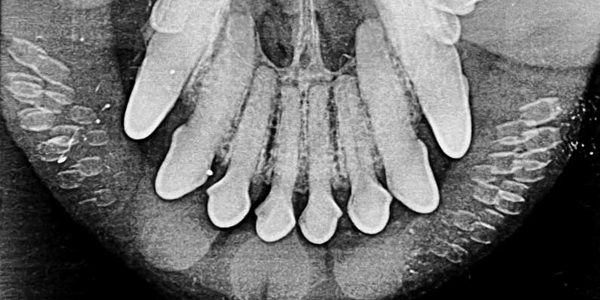

2025 X-ray contest results: Are you ready to see some crazy stuff?October 22, 20252025 They Ate What?! X-ray Contest results revealed. Prepare to see some crazy stuff!